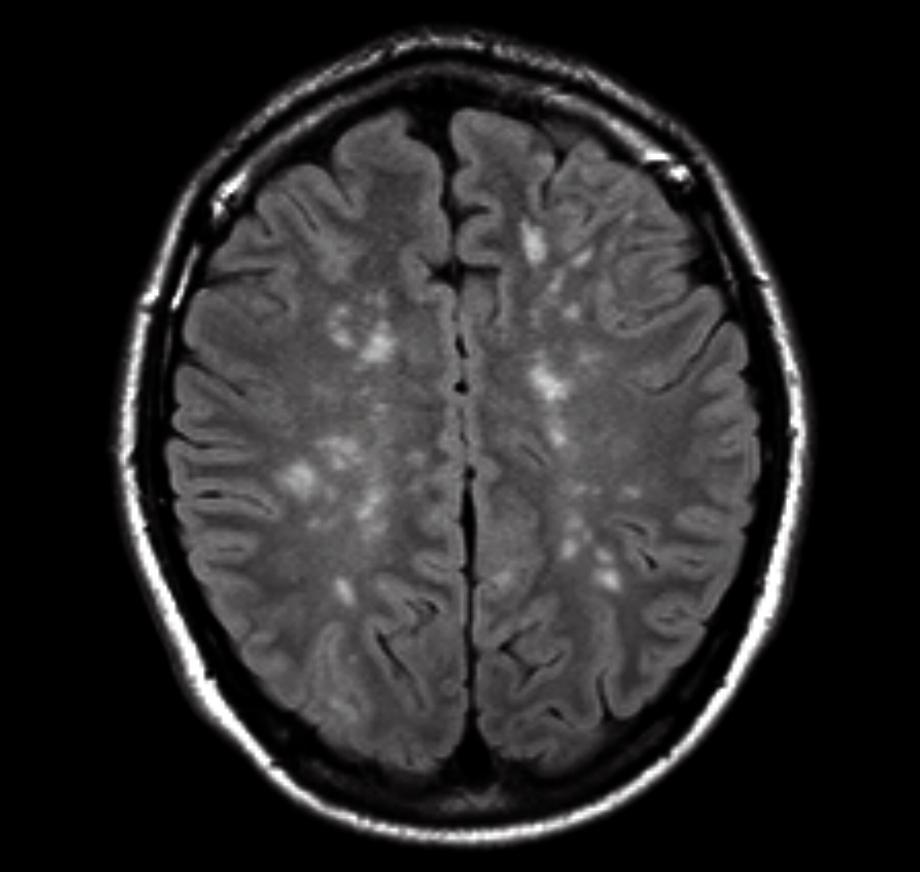

Een 23-jarige man werd na een auto-ongeval op de Spoedeisende Hulp gebracht. Hij had beiderzijds femurfracturen waarvoor hij een operatieve pen- en schroeffixatie onderging. Direct na de operatie was zijn bewustzijn niet-afwijkend, maar binnen enkele uren trad er een bewustzijnsdaling op. Patiënt had toen een Glasgow-comascore van E3M5V1 (openen van ogen op aanspreken, lokaliseren van pijnprikkel, niet spreken) en respiratoire insufficiëntie. Bij neurologisch onderzoek waren er geen focale neurologische afwijkingen. De bloedgasanalyse toonde een respiratoire acidose. Tijdens het maken van een CT-scan van de hersenen kreeg patiënt 2 maal een gegeneraliseerd tonisch-clonisch insult.